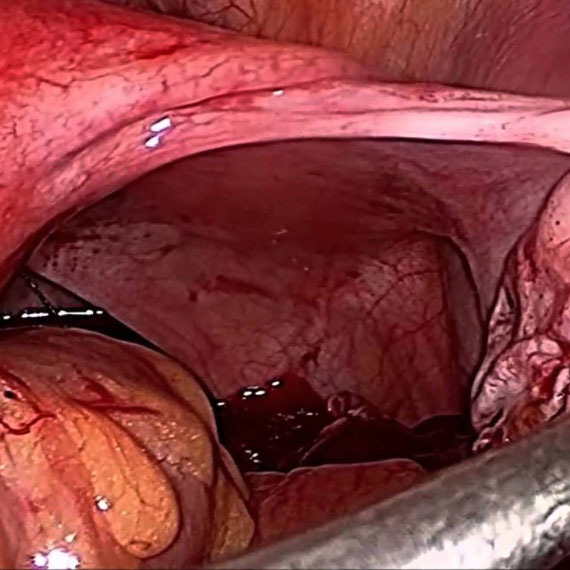

تنظير البطن الجراحي:

المجهزة بكل الأدوات والمعدات الإضافية اللازمة لإجراء معظم العمليات الجراحية النسائية بالمنظار وخاصة في مجال العقم مثل فك الالتصاقات وفتح البوقين، ومعالجة الإندومتريوز، واستئصال كيسات المبيض، والحمل الهاجر (خارج الرحم) والأورام الليفية.